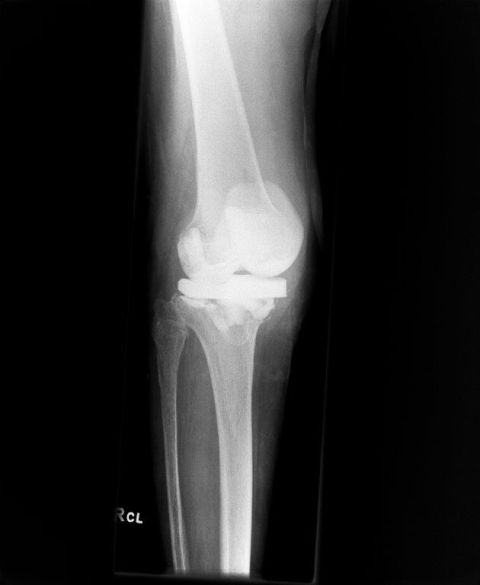

Interimsprothese bei Infektionsbehandlung Knie-TEP

Wenig auffälliges Röntgenbild bei Infektion des künstlichen Gelenkes